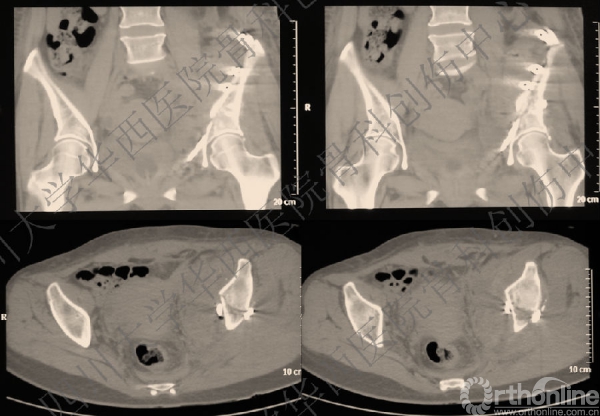

术前三维CT

做三维重建,进一步为手术做术前详细的计划,决定前方入路。